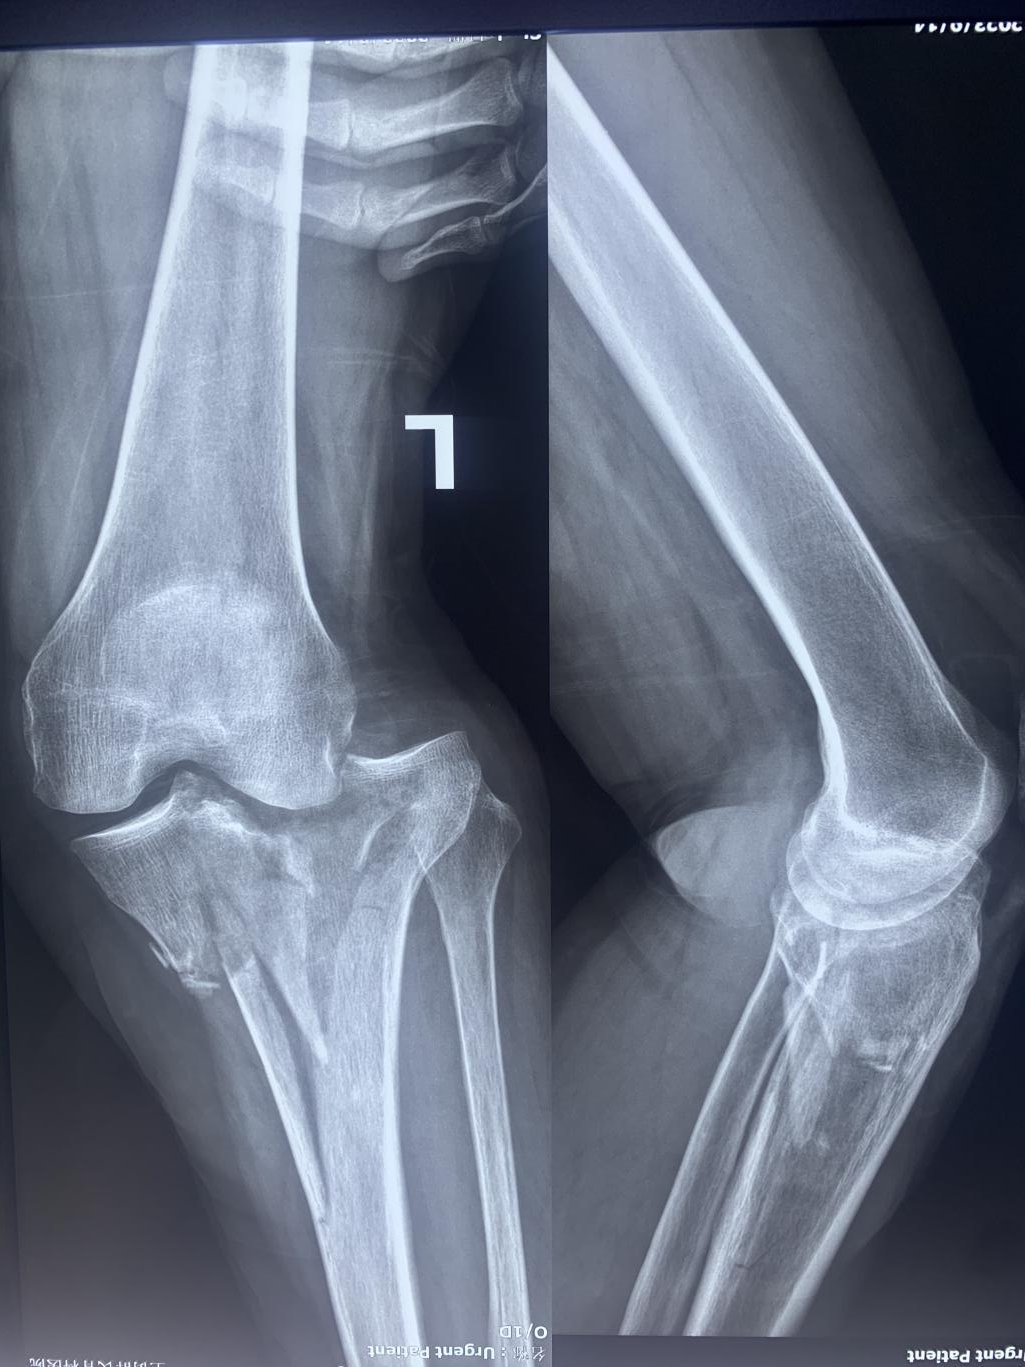

患者:女性,60 歲

以“摔傷左膝關(guān)節(jié)疼痛、活動(dòng)受限 2 小時(shí)”為主訴于 2023 年 9 月14 日入院。2 小時(shí)前工作時(shí)不慎滑倒,摔傷左膝關(guān)節(jié),被家人送至鄭州市骨科醫(yī)院診治。

手術(shù):Schatzker IV型脛骨平臺(tái)骨折的手術(shù)治療

入院 X 線: